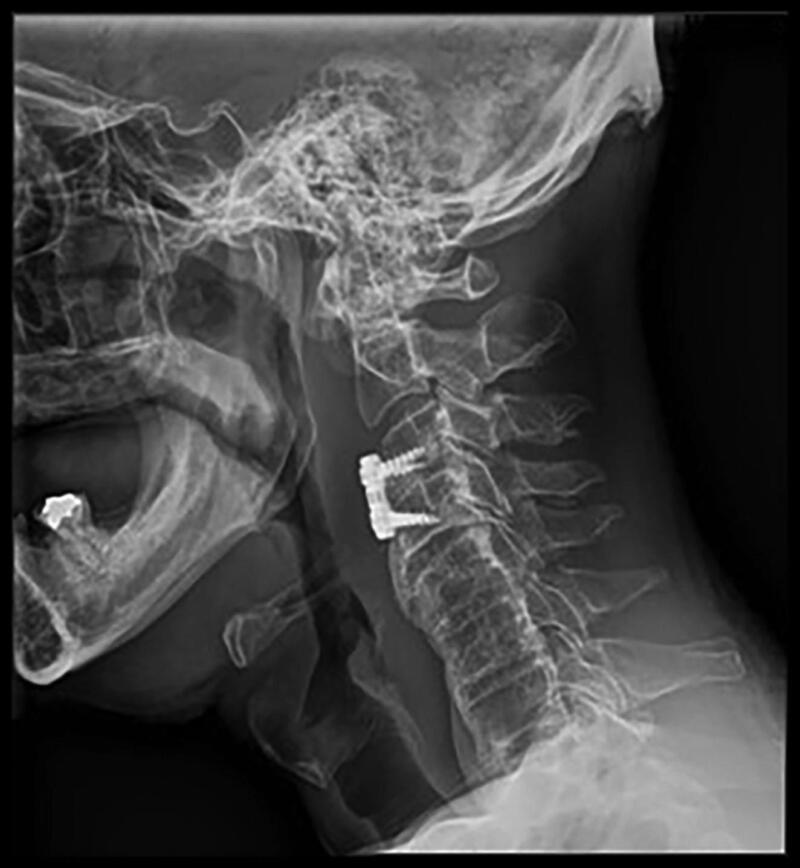

Nhiều hệ thống phân loại chấn thương cột sống đã được xây dựng nhằm xác định BN chấn thương cột sống nào cần được phẫu thuật, ví dụ phân loại của Denis, thang điểm Thoracolumbar Injury Classification and Severity (TLICS), phân loại Subaxial Cervical Spine Injury Classification System, phân loại của AOSpine (hình 16).

Hình 16. Phân loại chấn thương của AOSpine.

Mục đích của phẫu thuật là nhằm giảm sự mất vững của cột sống, ngăn ngừa biến dạng, và phục hồi hoặc ngăn ngừa khiếm khuyết thần kinh do chèn ép tủy sống và/hoặc rễ thần kinh (hình 17). Đường mổ nói chung gồm: trước, bên, sau, hoặc kết hợp, tùy thuộc vào vị trí tầng nào của đốt sống.

Hình 19. U cột sống. A. Sơ đồ mô tả các loại bệnh lý và vị trí tương quan với cột sống. B. mặt cắt dọc và C. ngang trên MRI cho thấy gãy xương bệnh lý ở L2 do di căn từ carcinoma thận. D. Phim Xquang nghiêng và E. thẳng sau khi mổ cắt bỏ thân sống L2 và làm cứng lối sau T12-L4.